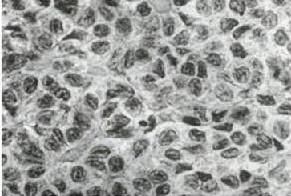

1、顆粒細胞瘤與小細胞癌、未分化癌

小細胞癌、未分化癌的瘤細胞分化差,細胞形態與顆粒細胞瘤細胞有時很相似,尤其在呈瀰漫性或類似濾泡樣排列時經驗不豐富的病理醫師會做出錯誤的診斷。但顆粒細胞瘤與後兩者在臨床症狀體徵、術中探查諸方面均有較明顯的不同。